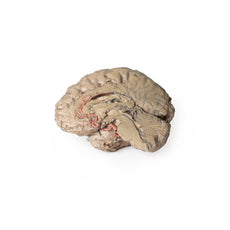

Within the endocranial cavity, the sectioned brain is slightly off the midagittal

plane, such that neither the superior sagittal sinus nor the third ventricle are

clearly defined - but the lateral ventricle is open and part of the fourth ventricle

is preserved between the pons and cerebellum. The gyri and sulci of the

cerebrum are not well separated, but the cingulate gyrus and corpus callosum

can be separated. Cross-sectioned views of the optic tract, pituitary gland,

superior and inferior colliculi, superior cerebellar peduncle, and transition

between the medulla oblongata and spinal cord are all visible. The tentorium

cerebelli and confluence/transverse sinus is positioned between the

cerebellar hemisphere and occipital lobe. Small portions of the posterior

inferior cerebellar artery, vertebral arteries, basilar artery, and posterior

cerebral and anterior cerebral arteries are visible in section.